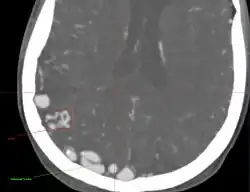

Rozpoznanie AVM opiera się na badaniach neuroobrazowych:

- tomografii komputerowej z podaniem środka kontrastowego (TK),